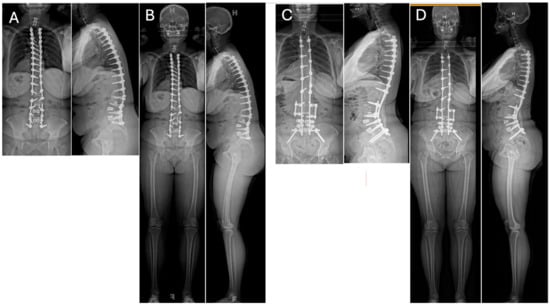

Pre-operatively, full-length standing radiographs should be obtained to evaluate sagittal parameters. A CT scan should be obtained to evaluate for pseudarthrosis or screw loosening not apparent on radiographic imaging. In patients with pseudarthrosis and maintained correction, revision arthrodesis with or without interbody fusion, along with the upsizing of any loose pedicle screws and rod replacement may be considered [23]. In patients with pseudarthrosis and persistent or recurrent sagittal malalignment, additional correction should be obtained with interbody cages and/or posterior-based osteotomies depending on the amount of correction required (Figure 1). Subsequent rod replacement with or without the placement of accessory or satellite rods can then be performed.

Figure 1.

36″ (A) and EOS (B) Postero-Anterior (PA) and lateral radiographs of a 49-year-old female who had a previous posterior spinal fusion from T3 to the pelvis which failed with broken instrumentation and pseudoarthrosis. The patient fell forward in the sagittal plane resulting in sagittal decompensation and malalignment causing debilitating pain. 36″ (C) and EOS (D) PA and Lateral radiographs 3 years post-operatively from the removal of instrumentation, revision T3-Pelvis posterior spinal fusion with quarter-inch stainless steel rods and pedicle subtraction osteotomy (PSO) at L3 using the satellite rod configuration at the PSO site.

Once the spine is re-exposed, primary instrumentation is typically partially or wholly removed, and the fusion mass is inspected for any defects requiring further bone grafting, decortication, or augmentation with biologic agents such as BMP [66]. Smith-Peterson osteotomies, PSO, or VCR may be performed to correct the focal PJK leading to instrumentation failure (Figure 2A,B), as residual kyphosis poses a significant risk factor for PJK/PJF recurrence [67]. The augmentation of fixation at the UIV to prevent recurrent PJF has also been heavily explored. This has historically involved large diameter UIV pedicle screws of maximum length coupled with polymethylmethacrylate (PMMA) cement augmentation to decrease screw pullout and the risk of construct failure [68,69]. Sublaminar tethering to augment the posterior ligamentous tension band cranially in the revision setting has also been explored but is primarily a prevention strategy [70]. A combination of medical optimization and thoughtful surgical technique are critical to achieving a successful result when treating PJK/PJF.

Figure 2.

Lateral 36″ radiographs (A,C) and sagittal CT reconstruction (B) of a 58 year-old female with history of combined L1–L5 anterior lumbar interbody fusion and T10-Pelvis posterior spinal fusion, complicated by infection requiring irrigation and drainage, who presented 1 year post-operatively with proximal junctional kyphosis (A,B). She underwent removal of instrumentation, revision posterior spinal fusion from T4 to T11 with Smith-Peterson osteotomy at T9-T10 (C). (D) Pre-operative EOS PA and lateral radiographs demonstrating proximal junctional kyphosis with global sagittal imbalance in the same patient shown in (A,B). (E) (top = cranial; bottom = caudal): Intra-operative clinical photo demonstrating the final construct used to address the proximal junctional failure and restore the sagittal plane following Smith-Peterson osteotomy at T9–T10. End-to-end connectors were utilized to connect the rods placed in the new instrumentation from T4 to T9 with the previously placed instrumentation. Side-to-side connectors were also placed at T8–9 on the left and T7–8 on the right and connected at T12 on both sides. (F) Post-operative EOS PA and lateral radiographs highlighting improved global alignment following removal of instrumentation, revision posterior spinal fusion from T4 to T11 with Smith-Peterson osteotomy at T9–T10.